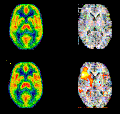

Κινέζοι ερευνητές ανακοίνωσαν ότι χάρη σε μια ειδικά σχεδιασμένη τεχνική μαγνητικής απεικόνισης μπορούν να εντοπίσουν μη φυσιολογικές συνδέσεις στους εγκεφάλους των παιδιών προσχολικής ηλικίας με αυτισμό, σύμφωνα με άρθρο που δημοσίευσαν στο επιστημονικό έντυπο Radiology.